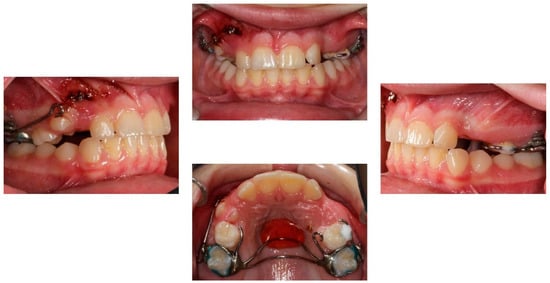

2.4. Treatment Results

After a total treatment of 3 years and 2 months, a group function occlusion was achieved, with positive overjet and overbite. No interferences in the non-working side were present with lateral movements. The canines underwent composite resin restorations to resemble the lateral incisors (Figure 9).

Figure 9. Post-treatment extra- and intra-oral photographs.